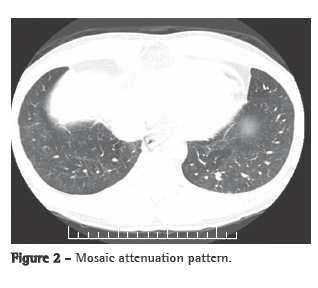

A transthoracic Doppler echocardiogram, which had been performed previously, showed moderate right heart enlargement, and pulmonary artery systolic pressure (PASP) was estimated to be 76 mmHg. A transesophageal echocardiogram demonstrated extensive thrombosis in the pulmonary artery trunk and PASP of 57 mmHg. Ultrasonography of the lower limbs revealed no signs of deep venous thrombosis. Lung perfusion scintigraphy, which was performed during hospitalization, showed low uptake in the view of the anterior and the apical-posterior segments of the left lung. The right lung was not visualized. Angiotomography of the chest revealed a large filling defect in the mediastinal and pericardial portion of the pulmonary trunk and arteries, there being enhancement of that defect after intravenous administration of contrast material (Figure 1a). In addition, there were predominantly peripheral nodules on the left (Figure 1b), as well as thickening of interlobular and peribronchovascular septa on the right, associated with upper lobe consolidation, moderate pericardial effusion and a mosaic attenuation pattern (Figure 2).